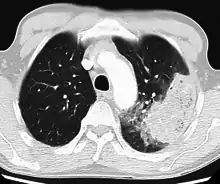

Cavitating pneumonia due to MRSA as seen on a CT scan

Bacteria are the most common cause of community-acquired pneumonia (CAP), with Streptococcus pneumoniae isolated in nearly 50% of cases.[41][42] Other commonly isolated bacteria include Haemophilus influenzae in 20%, Chlamydophila pneumoniae in 13%, and Mycoplasma pneumoniae in 3% of cases;[41] Staphylococcus aureus; Moraxella catarrhalis; and Legionella pneumophila.[21] A number of drug-resistant versions of the above infections are becoming more common, including drug-resistant Streptococcus pneumoniae (DRSP) and methicillin-resistant Staphylococcus aureus (MRSA).[24]